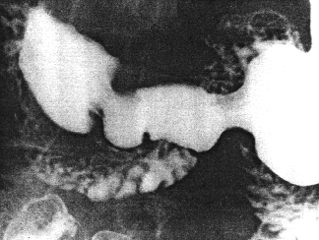

Case 20.5. H.O., 69 year old female, a known case of polycythaemia vera, splenomegaly, hepatomegaly and cholelithiasis, underwent cholecystectomy at which the stomach was proved to be normal. Because of a feeling of fullness in the epigastrium an upper gastrointestinal barium series was requested 10 days post-operatively. There was a persistent contraction of the pyloric sphincteric cylinder; occasionally it contracted maximally but never relaxed more than illustrated (Fig. 20.5). Normal cyclical contractions of the cylinder at 3 per minute were absent. The partial contraction of the cylinder fixed the pyloric aperture in the open position; at times duodenogastric reflux occurred through the patent pyloric aperture and contracted cylinder (Chap. 27). The contraction was associated with a concave impression of the base of the duodenal bulb. In view of the absence of an organic gastric lesion at operation, the condition was diagnosed as simple spasm of the pyloric sphincteric cylinder.

| Fig. 20.5. Case H.O. Spasm of pyloric sphincteric cylinder. Pyloric aperture fixed in patent position. Intermittent duodenogastric reflux. No gastric lesion detected at cholecystectomy |